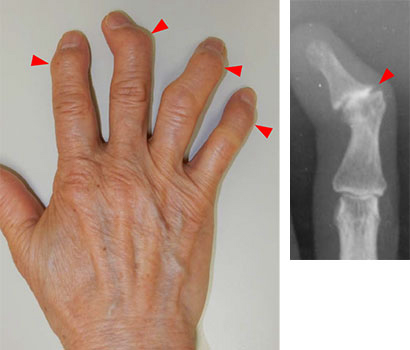

指先が腫れて変形する

「ヘバーデン結節」とは

どんな病気?

ヘバーデン結節とは

ヘバーデン結節とは、指の第一関節(DIP関節)に痛みや腫れ、変形が生じる、変形性関節症の1つです。

特に、中高年の女性に多く見られます。

へバーデン結節の主な症状

- 痛み

- 腫れ、熱感

- 変形、太くなる

- こわばり、動かしにくさ

- 痛みが引いたが、変形が残る